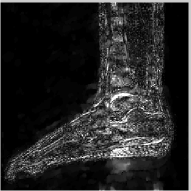

The reconstructions of an ankle image from its 4 fold Cartesian undersampled Fourier data, corrupted with zero mean complex Gaussian noise with a standard deviation σ=10𝜎10\sigma=10, are shown in Fig. 5. This is a really challenging case since the 1-D downsampling pattern is considerably less efficient than the 2-D random pattern used in the previous experiment. We observe that the non-local algorithm provides better reconstructions than the other schemes. Specifically, the TV scheme results in patchy artifacts. The DLMRI scheme results in blurring and loss of details close to the heel. The details are relatively better preserved close to the finger since there are no structures above or below it that aliases to it. By contrast to the classical algorithms, the degradation in performance of the non-local algorithm is comparatively small. The quantitative comparisons of the algorithms on this setting using different images are shown in the top section of Table IV.

Refer to caption

(a) Original

(b) DLMRI, SNR=12.96

(c) TV, SNR=15.02

(d) NLS, SNR=18.52

(e) Sampling pattern

(f) DLMRI error

(g) TV error

(h) NLS error

Figure 5: Comparison of the algorithms in the presence of noise. We consider the recovery of a 256×256256256256\times 256 MRI ankle image from its Cartesian Fourier sampling pattern (shown in (e)), contaminated by zero mean complex Gaussian noise with standard deviation σ=10𝜎10\sigma=10. The top row shows the original and reconstructed images, while the error images scale by a factor of five are shown in the bottom row. This is a challenging case due to the high 1-D undersampling factors and noise. We observe that the NLS scheme provides the best reconstructions with minimal alias artifacts.